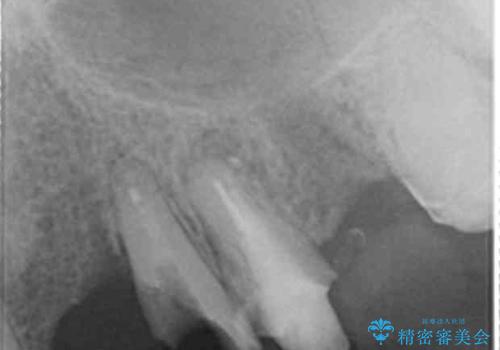

犬歯は歯ぐきの奥深くまで割れており保存不可能な状態でしたが、どうしても抜きたくないとのことでした。

健全歯質を歯肉縁上に出すためにしっかり挺出させたことで歯根長が短くなりましたが、仮歯で十分に保定した結果動揺度Ⅰ程度となり、ブリッジの支台歯にすることが可能と判断しました。